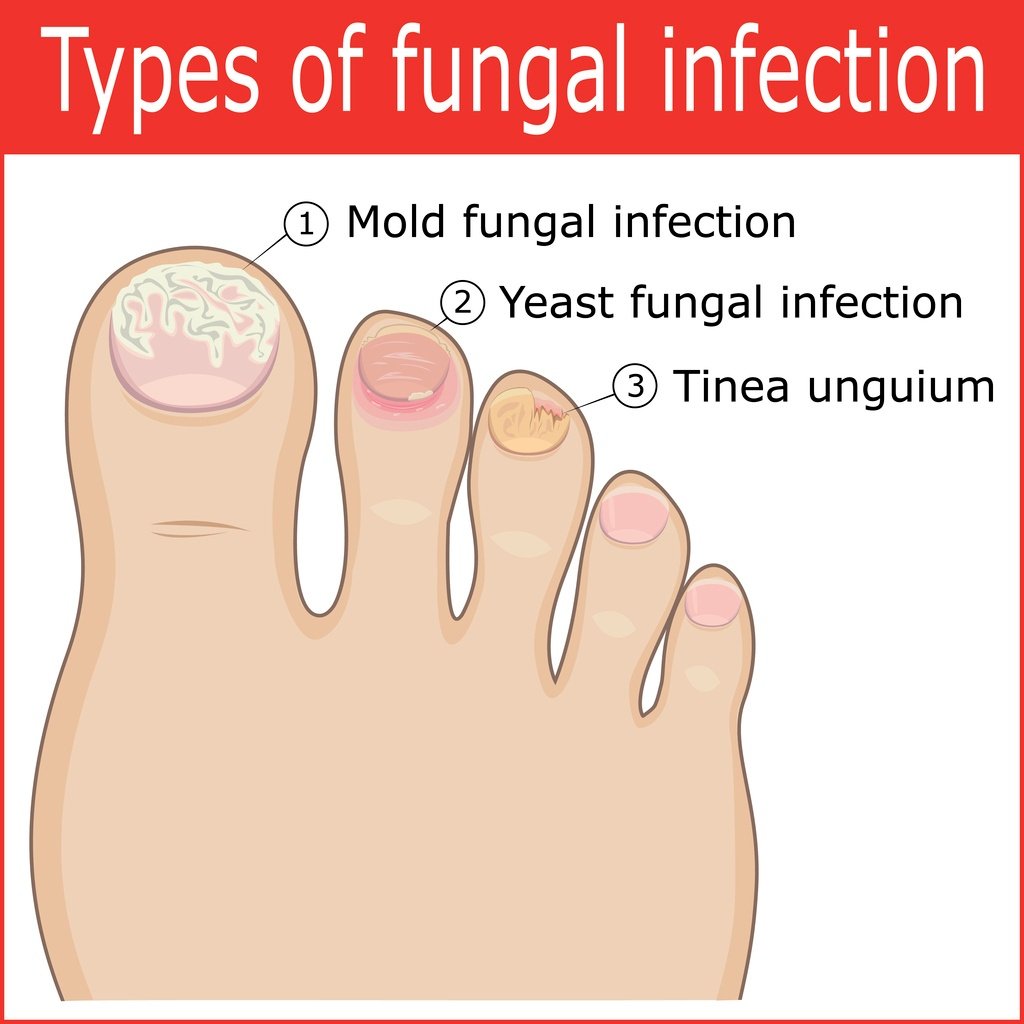

What Is Fungal Infection (Mycosis)?

Foot fungus types pictures – Awesome Nail

Toe Fungus – Treatment, Symptoms & Causes